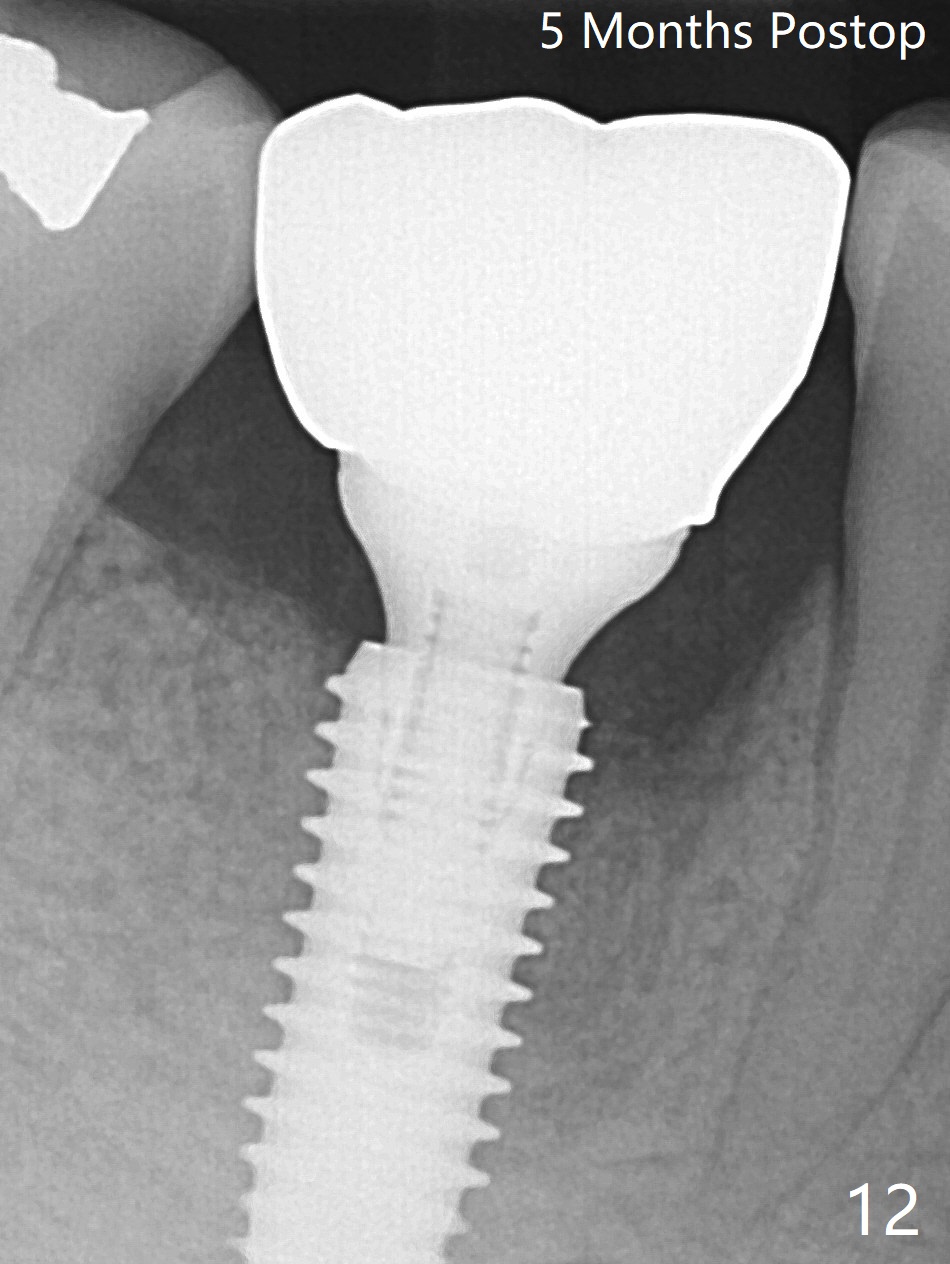

Preop oral Amoxicillin seems to be associated with reduction in the buccal and lingual (Fig.3 arrow) fistulae at #30, but there is mesiobuccal swelling (Fig.1 *) with 7 mm pocket (Fig.2). Osteotomy is initiated in the middle of the septum (Fig.3-5 S). As the osteotomy increases, it shifts mesially (Fig.6 arrow). Guided surgery is able to reduce shifting. A 5x13 mm implant is not seated completely (Fig.7) apparently due to osteotomy shifting. After removal of the bone from the osteotomy distally, the implant remains unseated with lower torque value (Fig.8). Following reuse of the 4.3 mm drill deeper by 1-2 mm, the implant is seated to a satisfactory depth (Fig.9 with increase in torque to 50 Ncm) with placement of Vera Graft (*) and a 7.5x4(3) mm abutment. After a second round of allograft placement (Fig.10 *), the implant is found to be 4 mm from the IAC. At the later stage of osteotomy, the coronal end of the septum is destroyed with loss of osteotomy depth landmark. It is apparent that the soft tissue landmark may be more reliable. The implant threads appear to be covered by the bone graft 3.5 months postop (Fig.11). The abutment is changed to 6.5x5(3) mm one before impression with minor margin prep. The bone density seems to increase 5 months postop, i.e., immediately post cementation (Fig.12) and 10 months postop (5 months post cementation (after retightening abutment), Fig.13 (*)). Periimplantitis develops mesiobuccally, consistent with bone loss 1 year 7 months post cementation (Fig.14 *); the implant seems to have been buccally placed. Bone graft is necessary with PRF or GEM21S if the vein is small and 6-month membrane with a hole around a 7.5x4(4) cemented abutment for easy wound closure. Take 5x5 CM CBCT to determine which wall has defect, buccal or lingual. Check mesial contact. If so, remove the crown, reseat the abutment (possible incomplete seating) and re-impress after bone graft.